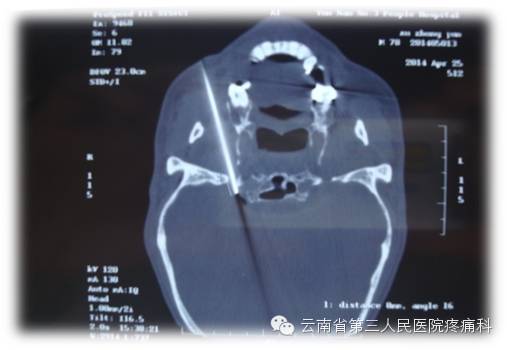

我科熟练开展经卵圆孔半月神经节射频热凝治疗

经皮穿刺半月神经节射频热凝术是治疗三叉神经痛最有效方法之一

治疗原理:三叉神经为感觉神经,其中神经纤维(AA纤维和AB纤维)能耐受较高温度,而痛觉神经纤维不能耐高温,CT引导三叉神经热凝术选择破坏痛觉纤维,使患者疼痛治愈。

治疗优势:安全、疗效好、不易复发、无副作用、费用比手术治疗低、创伤小、痛苦小、治疗时间短。

此项技术的重要环节在于靶点穿刺的准确性,利用CT引导或3维重建技术,可以使穿刺成功率和有效性大大提高。证疗效及安全的另一重要环节为热凝温度选择科学性。